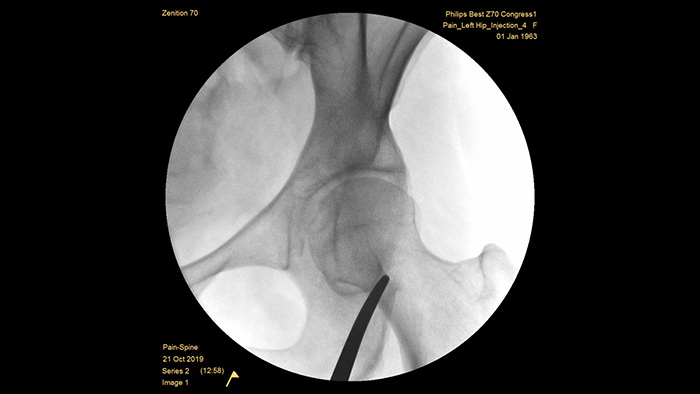

Philips has built a reputation for excellence in imaging and dose efficiency over half a century of experience in developing mobile C-arm systems for the surgical environment. Our Zenition mobile surgery solutions are built on a comprehensive approach to dose management. It provides clinically relevant image quality during interventional procedures for pain management applications, while efficiently managing radiation exposure to patients and medical staff.

Unique pre-configured pain management examination setting allows the users to easily set up the system during the interventional procedures for pain management.

MetalSmart automatically excludes metal artifacts caused by metal implants to provide higher image quality and efficient dose control for pain procedures and patients with metal implants, compared to systems without metal exclusion. BodySmart promotes first-time-right imaging and dose efficiency by automatically adapting the measuring field to the area of interest.